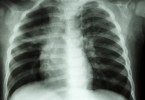

心室间隔缺损是最常见的先天性心脏畸形,超声显示心室间异常通道。小型缺损可能无症状,大型缺损会导致左右心室血液混合,可能引发胎儿心力衰竭。出生后需评估缺损大小决定是否手术修补。

法洛四联症包含四种心脏畸形,超声表现为右心室流出道狭窄、室间隔缺损等。胎儿可能出现缺氧表现,出生后需分期手术治疗。孕期监测重点为肺动脉发育情况。

大动脉转位时主动脉与肺动脉位置互换,超声可见大血管起源异常。这种畸形导致体循环与肺循环分离,胎儿依赖卵圆孔和动脉导管维持生命,出生后需立即行动脉调转术。